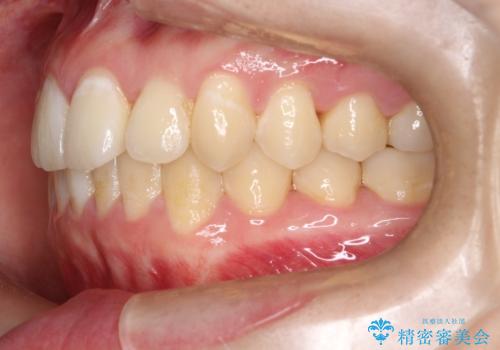

前歯が前後反対にかんでいる インビザラインによる矯正

- 前歯のがたつきを気にされて来院されました。

上顎の前から二番目の歯が内側に入り込んでおり、前後反対にかんでいる状態でした。

歯と歯の間にわずかに隙間を作り並べる計画としました。

しっかりとマウスピースを使用していただけたので、順調に治療を終えることができました。